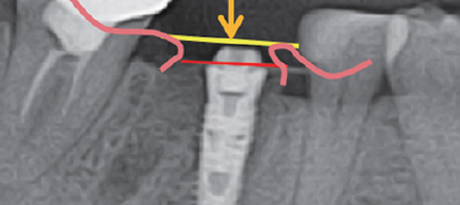

BOSS Type 1(BOSS Abutment)과 호환 사용 시술 시 고려 사항

Implant 식립 깊이

전후 Bone Level보다 1~2mm 깊게

BOSS Abutment 높이

전후 치은 높이보다 1mm 낮게